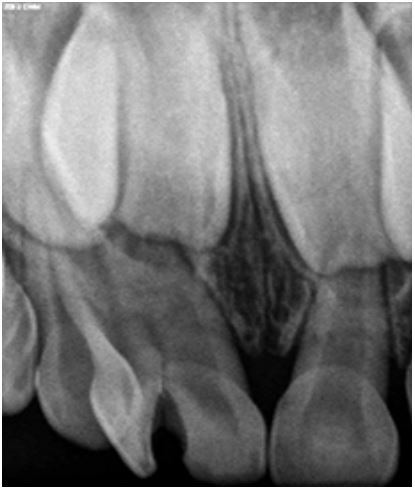

A 5-year-old male patient reported to our clinic with the chief complaint of decayed upper front teeth region. Patient presented with an episode of spontaneous pain which was relieved on medication. Medical history was non-contributory. Clinical examination revealed a geminated deciduous maxillary right central incisor (51, ISO system) having a large crown, showing a groove between non separated crowns on labial surface (Figure 1). It was noted to be non-vital on examination with electric pulp tester (Pulp tester C-pulse, Foshan CICADA Technology, China, input DC 9 V, output 80 V, 90 mA). Radiographic examination revealed two independent pulp chambers and two fused roots but with individual canals within (Figure 2). History, clinical and radiological findings pointed at the diagnosis of chronic irreversible pulpitis and pulpectomy was planned. Local anaesthesia (2% Lidocaine) was administered and rubber dam application was done. Access was achieved from the palatal surface and two canals were located; one, mesial and the other distal. Pulp extirpation and debridement was done by ProTaper Gold rotary files (Dentsply Maillefer, Ballaigues, Switzerland) upto F1. Irrigation of root canal was done with 2.5% sodium hypochlorite and saline. Obturation was done with Metapex (Meta Biomed Co. Ltd, Cheongju, Korea) (Figure 3). Access cavity was restored with glass ionomer cement till the cervical third and final restoration completed with composite.

Figure 1: Groove on the labial aspect of tooth.